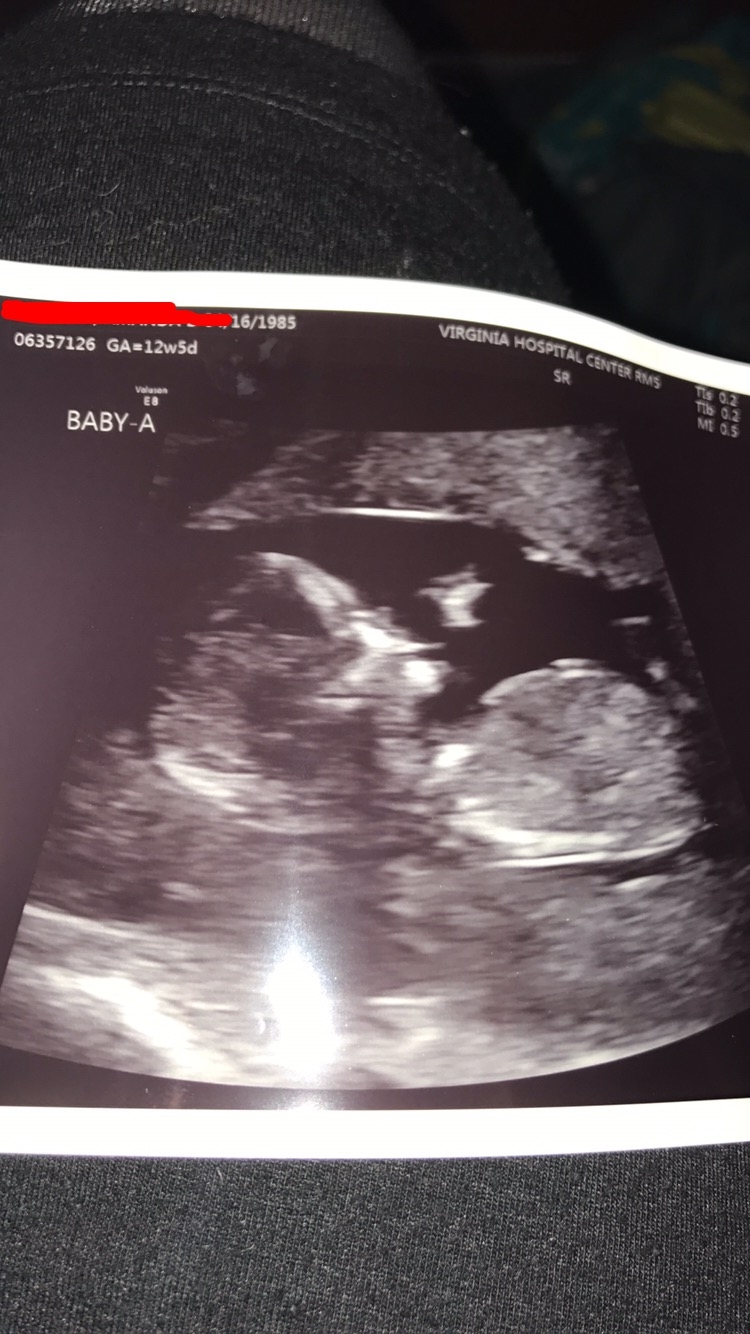

12w3d NT scan. NT results were good (as expected since NIPT was good). Pretty cool that you can see the jaws opening and closing, with what I guess are tooth buds, huh?

And so amazing (except for the tech with a pretty crappy attitude but I understand they might need to be a bit detached).

I swear that the images in real time were very much like a real baby rather than the blobby image. Due date was moved up a day, but we're still going with Jan. 14. Whole family is now calling the baby, "The Blob". Haha!